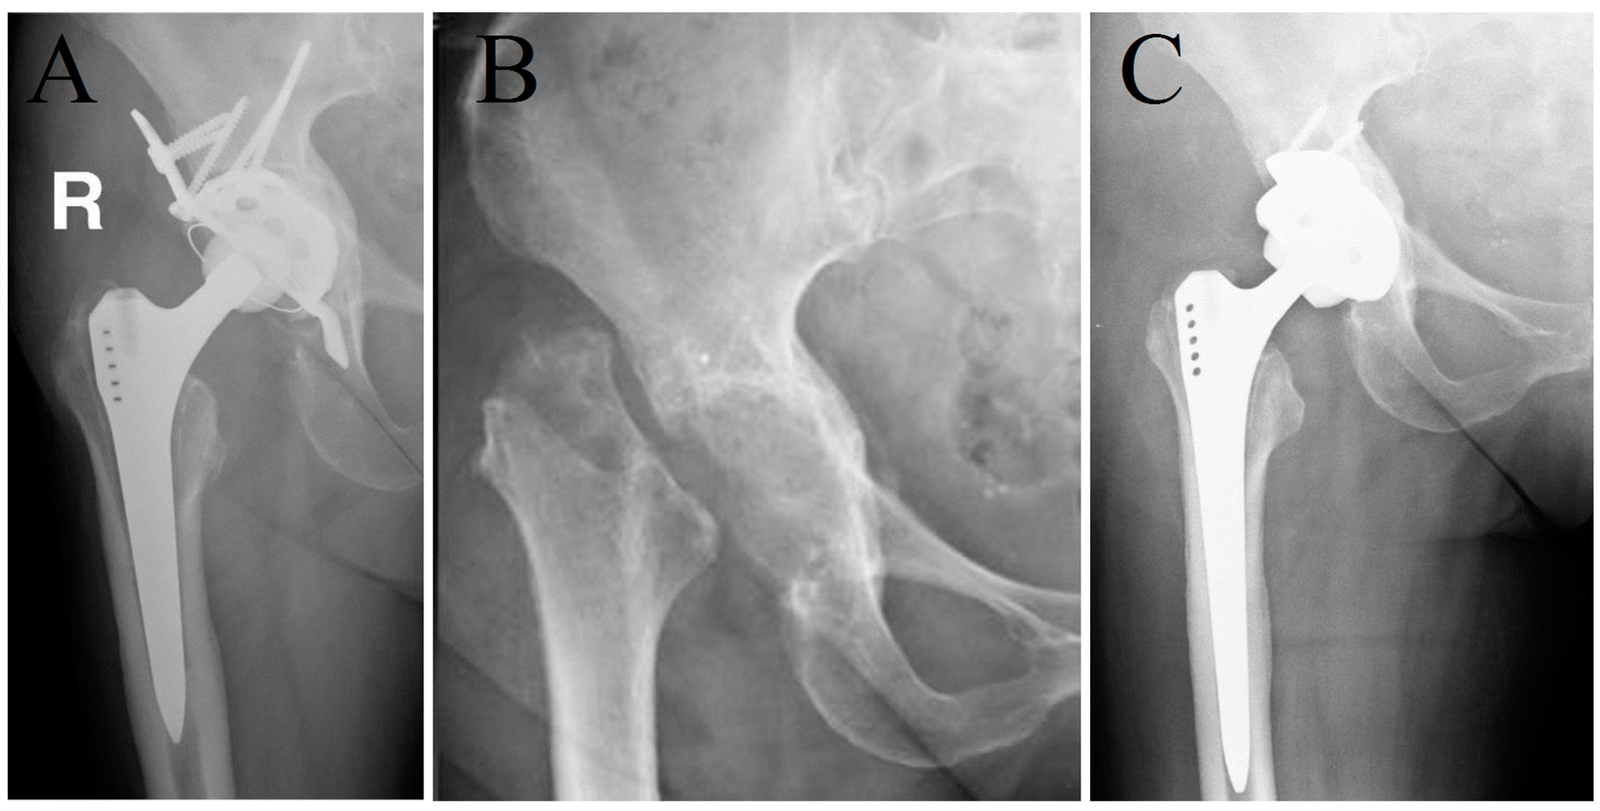

2. Hemireplacement arthroplasty: Either of the articulating surfaces is removed or replaced by prosthesis of similar shape and size, e.g. Austin Moore’s prosthesis in the fracture neck nonunion. Here one of the articular surface is excised and replaced with prosthesis. Other normal articular surface is left behind.It is commonly done in hip joint where in femoral head is removed and prosthesis is placed.

3. Total replacement arthroplasty: Here both the articular surfaces are excised and replaced by prosthetic components; the larger joint is replaced by a metallic prosthesis and the smaller joint by high density polyethylene. Both the components are fixed byacrylic cement, e.g. total hip replacement for advanced intractable osteoarthritis or rheumatoid arthritis. It is commonly done in hip joint. Often used in knee and other joint.

Types of hip arthroplasty:

1) Cup or mold arthroplasty: In cup arthroplasty, the acetabulum and the head of femur are reamed down to an un traumatized surface and an appropriate size metal cup is fitted over the head of femur

2) Total hip arthroplasty: In total hip arthroplasty, the femoral head and neck, ream the femoral canal and insert a metal femoral component (which includes head neck and steam) into the femoral shaft.